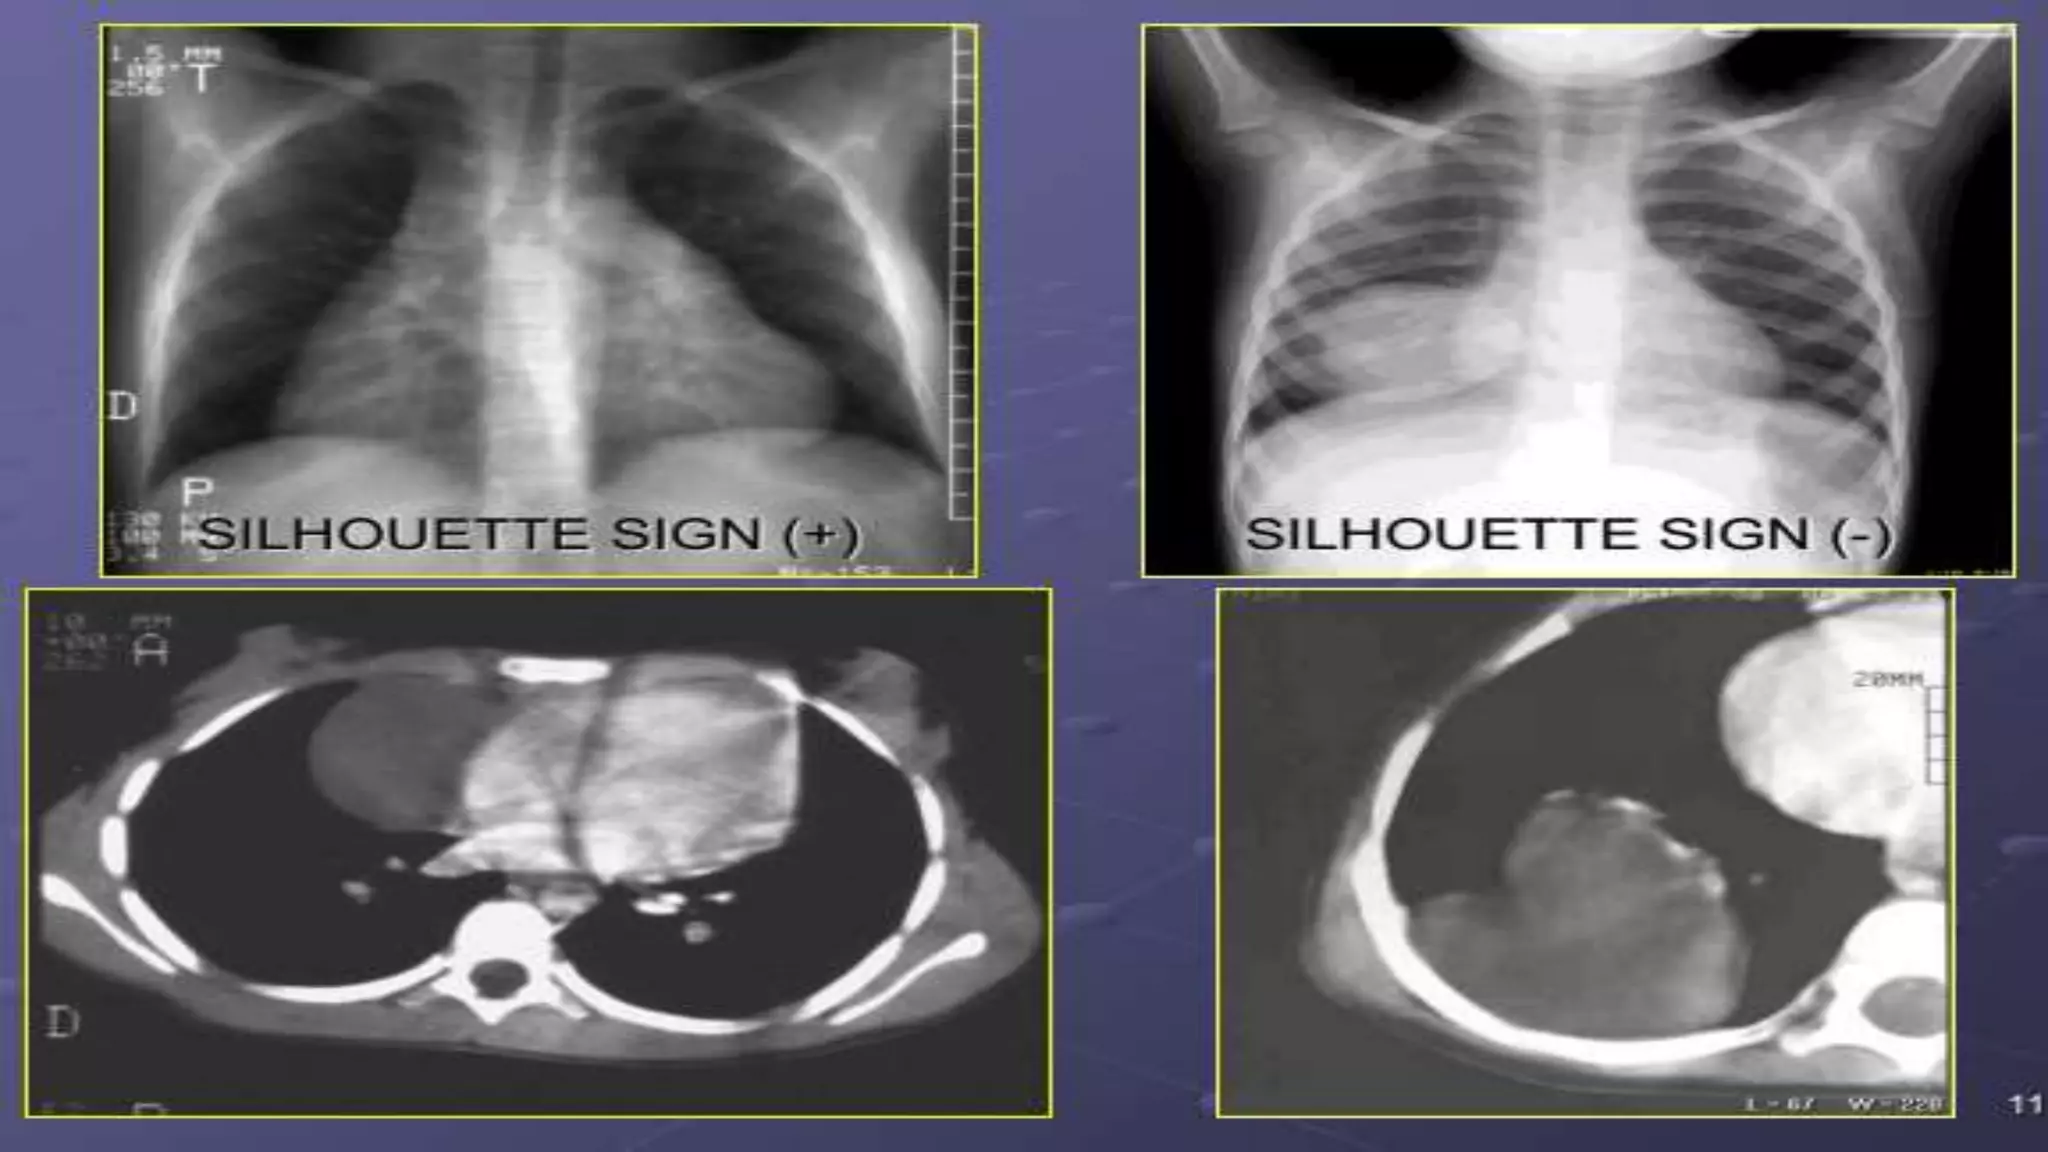

 Hai bộ phận cùng đậm độ, nếu cùng một măt phẳng thì không thấy

ranh giới của nhau.

 Hay 2 bộ phận khác đậm độ cùng mặt phẳng hoặc cùng đậm độ

nhưng khác mặt phẳng thì thấy được bờ của nhau.